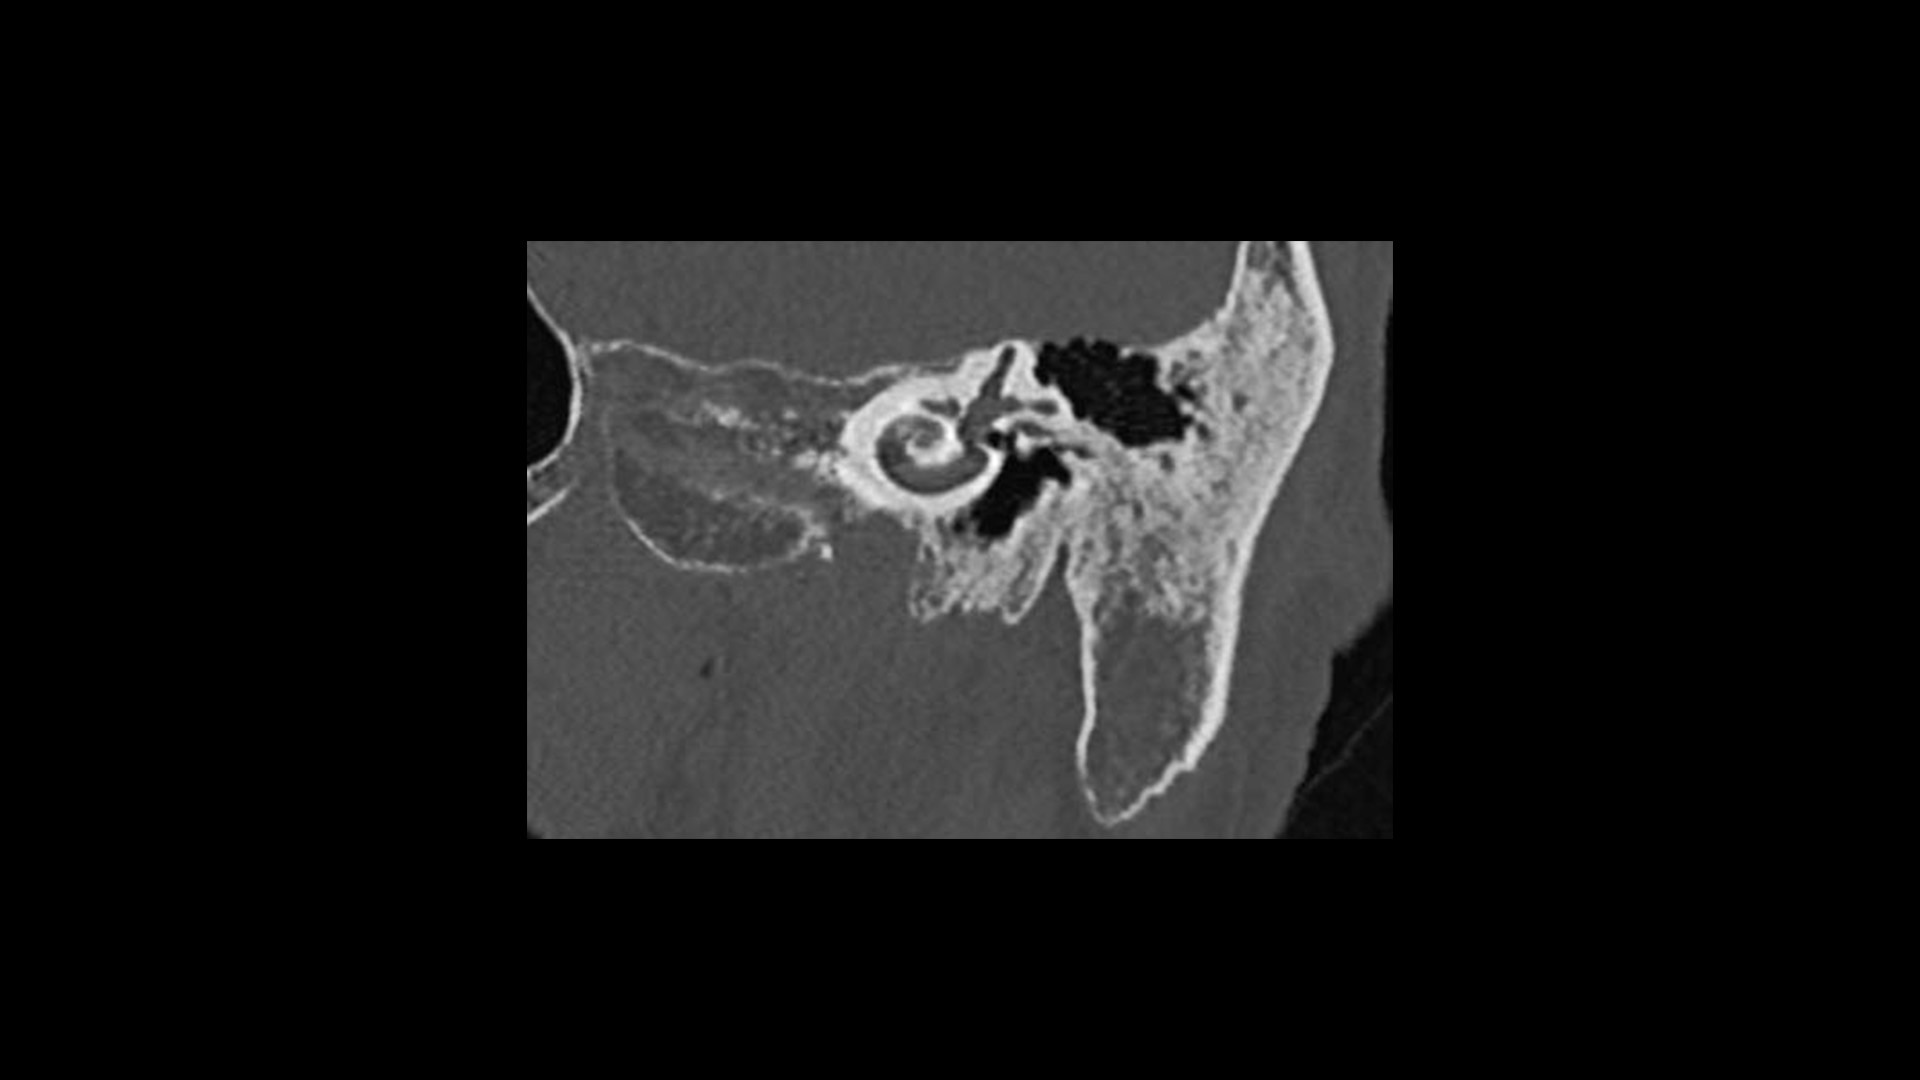

True Enhance DL is a deep learning-based processing method intended for contrast enhancement of single energy images. True Enhance DL uses a dedicated Deep Neural Network (DNN) trained to estimate monochromatic, 50 keV GSI images from single-energy X-ray. This technology brings four deep learning models that the user can choose depending on different contrast enhancement phases by clinical tasks.

TrueFidelity™ DL is our state-of-the-art image reconstruction technology that uses a DNN to generate high-definition, low-noise CT images. It produces images with exceptional sharpness, low-contrast image quality performance and your preferred noise texture, at the same dose.¹